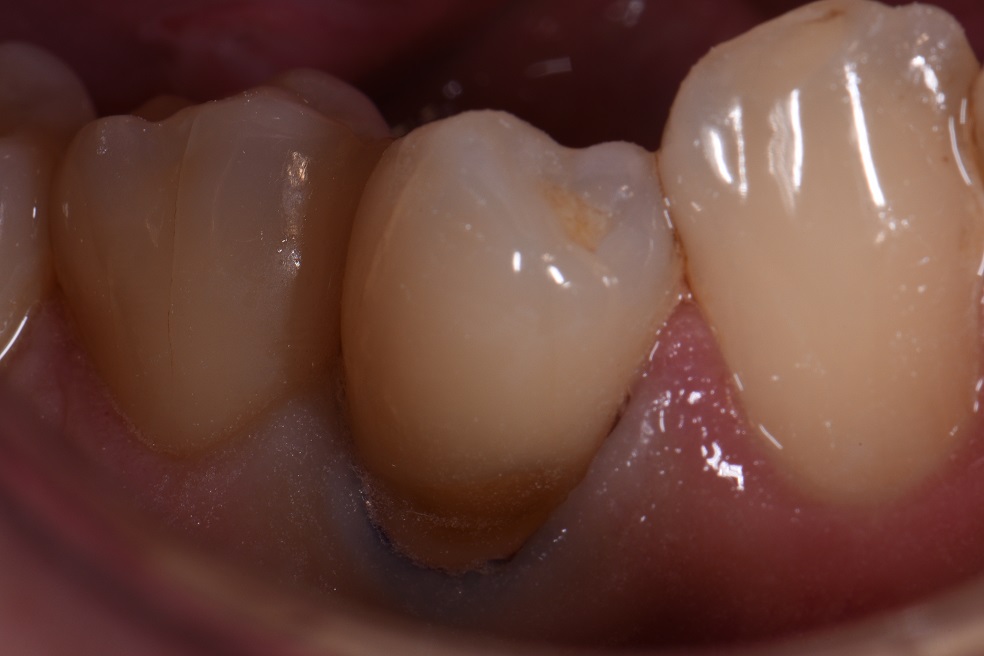

#ClassVMagic #GC #EssentiaU #BlendtonoEnd (kind of)